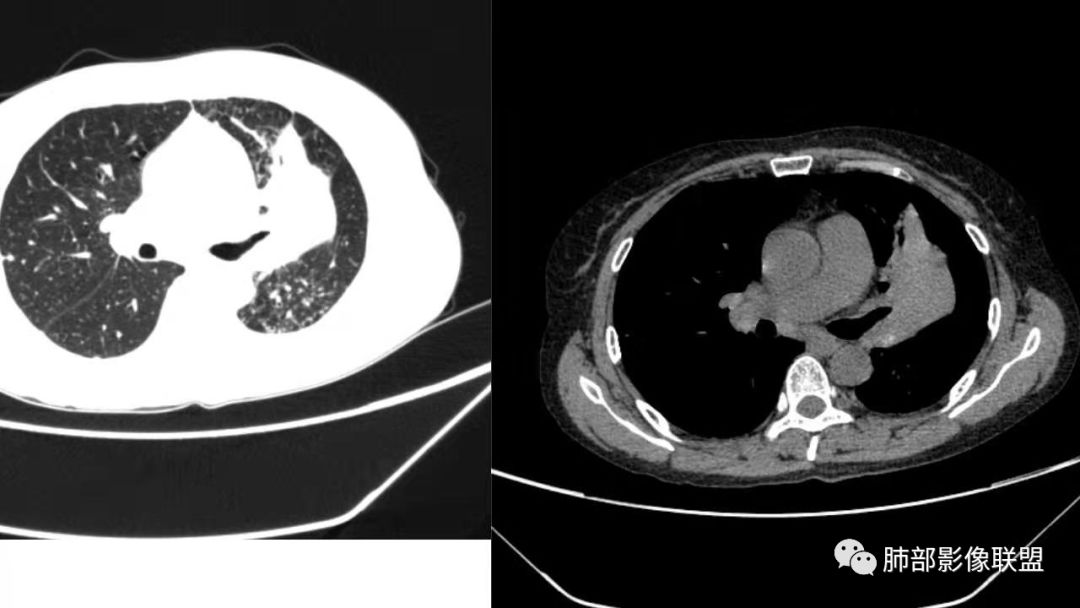

左肺团块影,形态不规则,其内见充气支气管征,增强扫描明显强化,其内见液化坏死区。下叶基底段见斑点状密度增高影。双肺门见斑点状钙化影。疾病谱有结核,增强除外了。肺癌和淋巴瘤鉴别。

病灶远端有扩张支气管,树芽,实变,纵隔肺内淋巴结钙化,考虑肺结核。

强化不是很明显,我考虑炎性病变,结核放第一位。

支气管是通畅的

整个上叶尖后段阻塞性肺不张的表现,从强化来看没有异常结节状或肿块样强化,肿块内部点状钙化、纵隔多发小淋巴结、下叶背段有树芽征,整体来看支持肺结核,让人不放心的是最后一幅冠状位重建的图像尖后段支气管堵了,而且有轻度的隆起,所以很难除外粘液表皮样癌(女性,鳞癌可能性小),如果是我写报告肯定会建议纤支镜检查

中年女性,反复咳嗽咳痰4月,加重半月,咳嗽,咳黄痰。胸CT:左肺体积缩小,左肺上叶病变,病灶内可见支气管征,病灶边缘可见棘突样改变,病灶周围可见结节状卫星灶,纵隔可见淋巴结肿大,部分淋巴结可见钙化灶。增强CT病灶内可见低密度坏死区,冠状位病灶内支气管可见扩张,病灶整体呈收缩,考虑患者为良性慢性感染性病变,结核?放线?,建议支气管镜检查。

考虑结核伴混合感染。中青年女性,持续低热、不正规抗感染症状加重。左上肺低密度肿块,左上固有段支气管未显影(结核侵蚀干酪样坏死),左上舌段支气管通畅但增厚变形。左下肺树芽征新发支气管播散。鉴别:粘液腺癌

左上叶实变不张,膨胀生长,上叶开口阻塞?,病灶内支气管扩张,明显延迟强化,内见低密度灶及点状钙化,周边见小叶间隔增厚丶结节,右斜裂结节

中年女性,反复咳嗽咳痰4月。胸CT:左肺上叶块状病变,病灶内可见支气管征,边缘见棘突样改变,周围可见结节状卫星灶,纵隔可见淋巴结肿大,部分淋巴结可见钙化灶。增强CT病灶内可见低密度坏死区。病灶整体呈收缩,考虑为良性病变,结核可能性大,建议支气管镜检查。

左肺病变支气管有狭窄后扩张,有部分钙化,符合结核,但叶间裂有膨隆,支气管有受压变窄表现,部分病灶内有血管,不能排除腺癌的可能,所以考虑肺结核合并腺癌可能

中年女性,慢性咳嗽,咳痰病史4个月,左肺上叶可见一团块状密度增高影,边界清,未跨叶裂,边缘有收缩有膨隆,周边可见结节影及树芽,周边部分小叶间隔增厚,内部可见点状坏死及血管包埋,有支气管充气征,部分支气管扩张,考虑淋巴瘤可能性大,鉴别结核

左肺大片状实变影,边缘彭隆,近端支气管堵塞,上端部分包绕支气管,平扫密度欠均匀,其内可见小点状钙化影,增强后可见血管穿行并伴有低密度坏死/粘液?临床有发热,Ca199偏高,综合考虑1:腺癌(粘液腺癌,粘液表皮样癌,腺样囊腺癌)2淋巴瘤

左肺上叶软组织肿块,密度不均匀,边界清晰,不均匀强化伴坏死,支气管走行僵直

中年女性,咳嗽咳痰4月,加重半月。偶发热,肿瘤指标升高。病变主要位于左肺上叶后部,实变,病灶大部边缘平直、局部膨隆,邻近叶间裂局部向后膨隆,病变密度整体较均匀,见小斑片状低密度区及点状钙化影;左肺上叶舌段支气管可疑截断,病灶内支气管走形迂曲变形、不规则狭窄扩张、部分支气管内粘液栓形成,可见局部扩张支气管似小空洞相连,病灶内血管走形自然;糊墙。病灶前缘小叶间隔增厚,平滑;左肺下叶支气管管壁增厚,见部分树芽征及腺泡结节,边缘不清。纵膈及双肺门部分淋巴结钙化,隆突下淋巴结增大;未见胸腔积液。1.左肺上叶病灶倾向于恶性肿瘤,腺癌可能,排除粘液腺癌;2.左肺下叶少许炎症;

晨读:左肺上叶实变,边缘不整,部分膨隆,其内支气管有狭窄有扩张,周围小叶间隔增厚,左肺下叶背段可见气腔结节,树芽征,边缘模糊,肺门及纵膈淋巴结钙化,考虑结核。鉴别肺炎型肺癌。

左上肺片状高密度影,其内有充气支气管征,血管造影征,叶间裂明显膨隆,支持粘液腺癌,鉴别于淋巴瘤、结核

中年女性,慢性咳嗽,右肺上叶块影,边缘膨隆+平直,肺容积略有缩小,部分支气管通畅、先狭窄后扩张,有树芽、网格,淋巴结钙化,强化轻,不均匀,内部低密度坏死,粘液栓,血管受累纤细,胸膜冠状位似有栽桩,良恶的特点皆有,首先考虑结核,肿瘤不敢排除,需要进一步结合临床